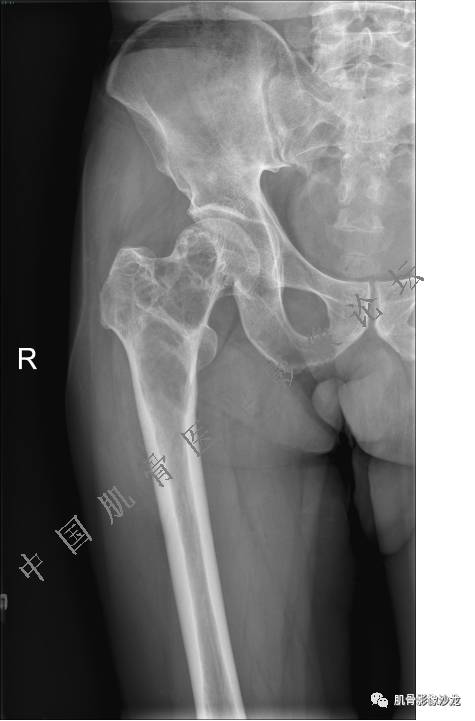

股骨近端占位性病变4例影像讨论

主诉:右髋及右膝部疼痛3月余

现病史:3月前打球时自觉右大腿肌肉拉伤后右髋及右膝部疼痛,自服“活血化瘀”类药物(具体不详)后自觉疼痛缓解,2月前打球时再次扭伤,右髋及右膝部疼痛明显,行走时疼痛加重,自服药物治疗,效果不佳,遂来诊。

Echo 20:23 我个人觉得,17岁男性,病灶发生在原干骺端区域,溶骨性骨质破坏,似有肿瘤骨,有软组织肿块形成,从常见病发生率来说,骨肉瘤还是要考虑的